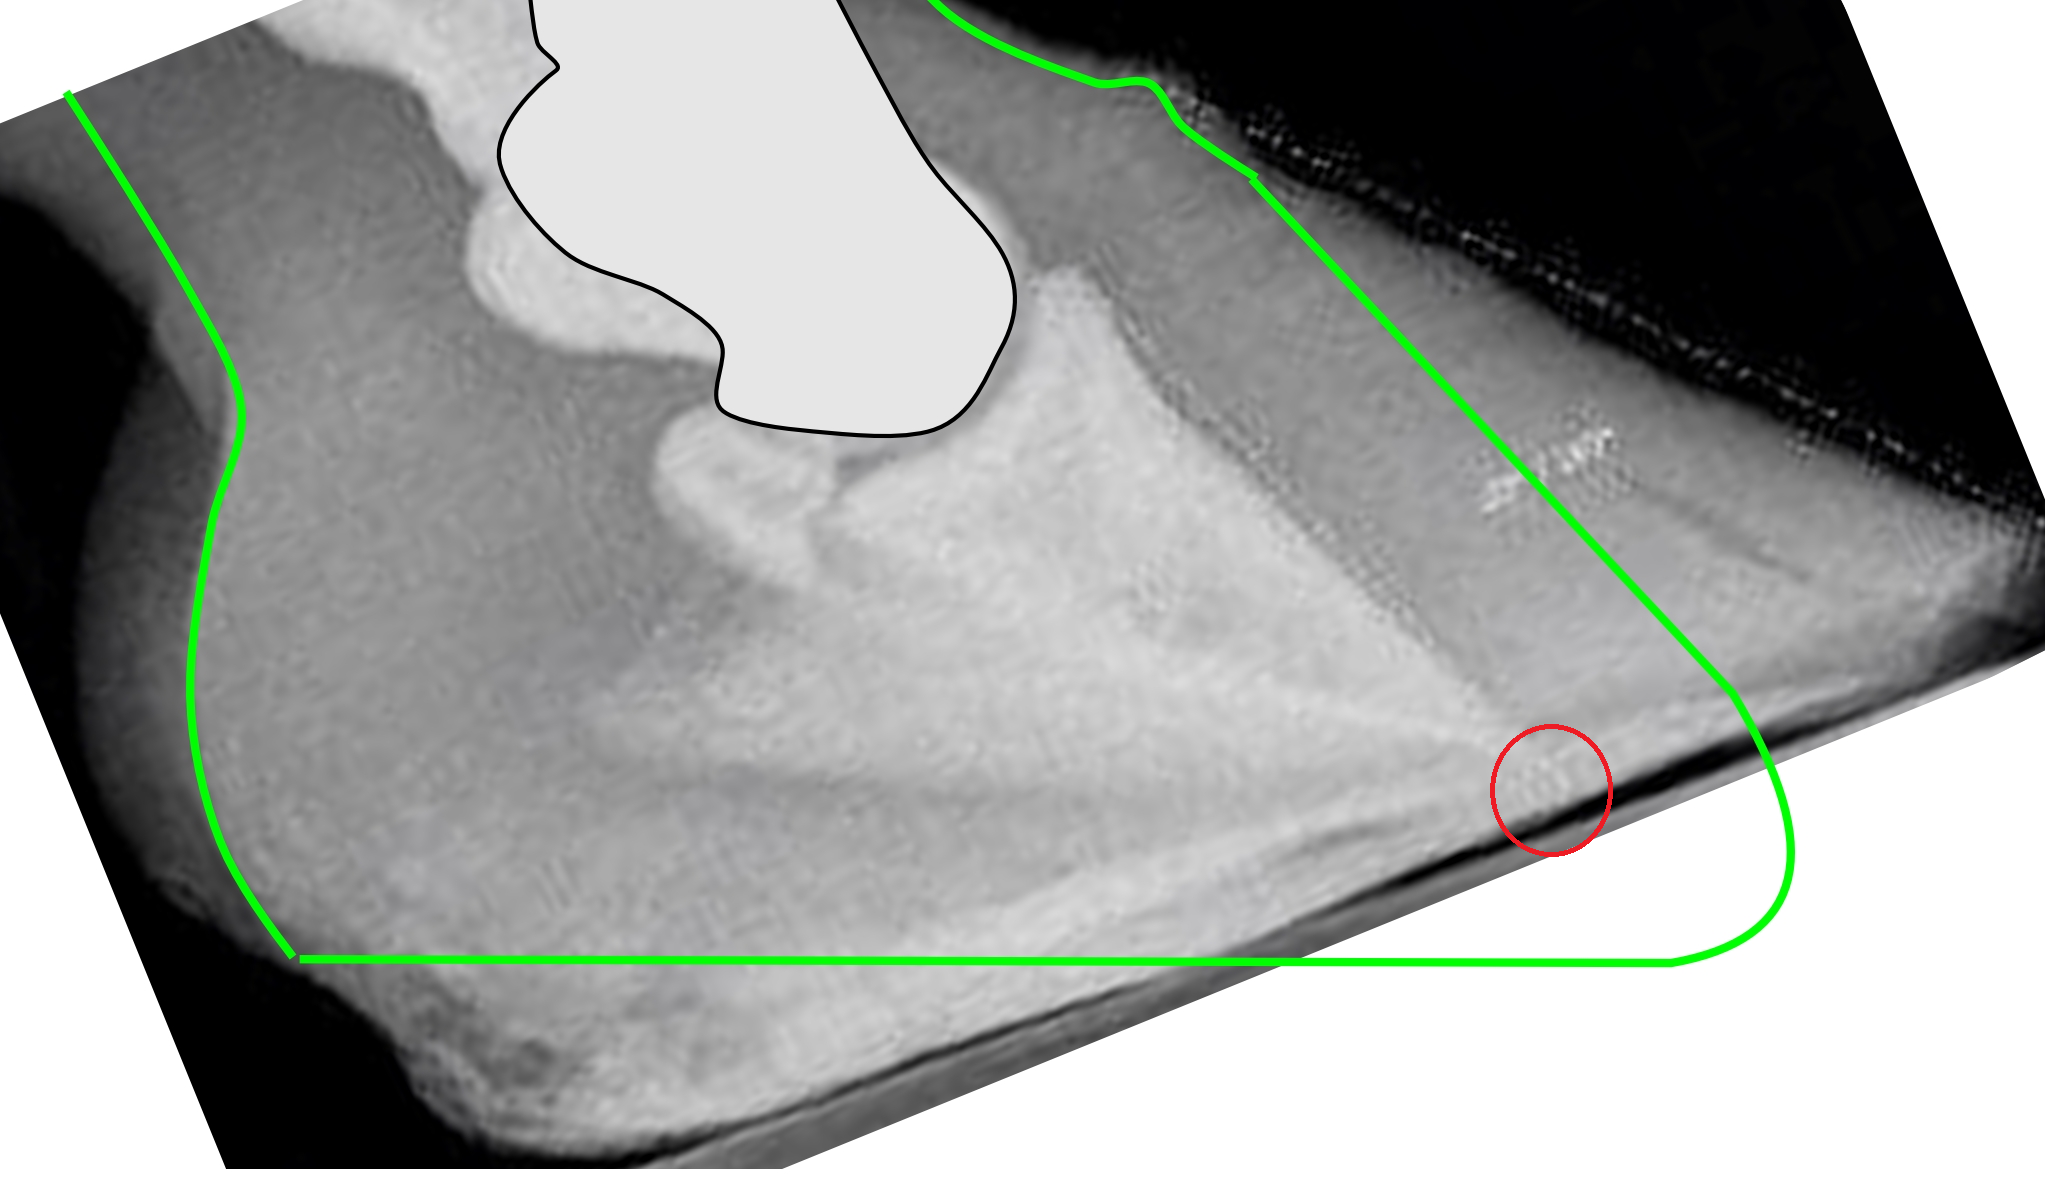

What does such a hoof look like from the outside? It looks quite low with an almost horizontal coronary band and a long toe. The horizontal coronary band says that the heel is too high and the coffin bone is pointing downwards, the low coronary band has put the coffin bone tip close to the sole, and the long toe is usually laminitic. The natural hoof shape (marked green in the picture below) sticks out below the photographed hoof because someone has trimmed the bottom (thinned the sole) in the front part of the hoof to make the toe look steeper. This is common but very serious, and difficult to rehabilitate.

If the coffin bone was originally parallel to the toe wall, as the white marking suggests, and then “rotated” down to what the radiograph shows, where did all the materia in the red triangle go?

There is never any void inside the hoof where this missing tissue, or the coffin bone, could go. But the missing tissue must have gone somewhere, or?

The answer is that it didn’t go anywhere because the bone has not moved. It was never up by the hoof wall; the hoof wall was down by the coffin bone, and got pressed up by ground pressure after suffering laminitis.

The red line indicates the alleged original angle of the coffin bone.

The green line indicates the current angle of the coffin bone.

The yellow arrow points to pristine sole corium.